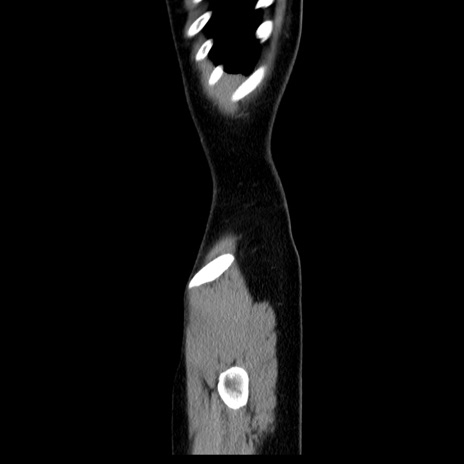

MRI(4日後)